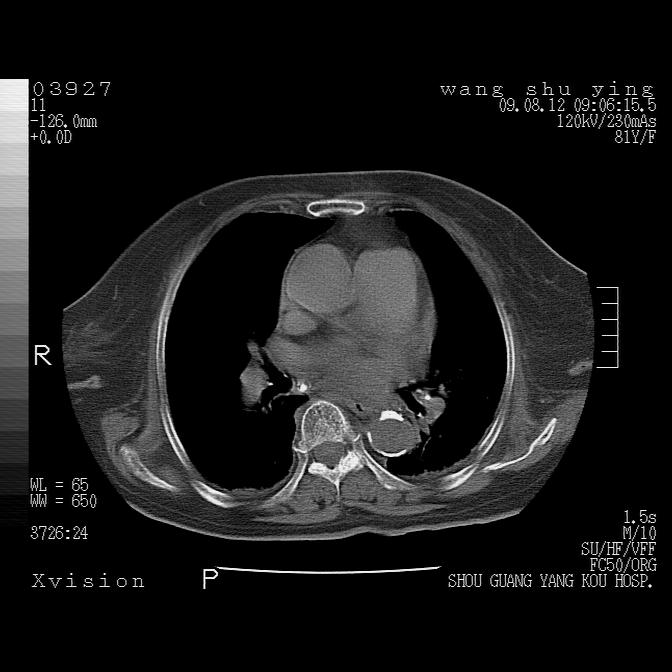

以下是引用帅河马在2009-8-12 12:59:00的发言:[br]两肺感染性病变伴双侧胸膜肥厚。[br]左侧甲状腺腺瘤不除外。[br]腹水+心包积液。[br][br][本贴已被 帅河马 于 2009-8-12 13:14:32 修改过]

以下是引用sdzyy在2009-8-12 18:17:00的发言:[br]两肺感染性病变伴双侧胸膜肥厚。[br]左侧甲状腺腺瘤不除外。[br]腹水+心包积液。[br]支持

以下是引用随光逐影在2009-8-12 19:42:00的发言:[br]1)两肺感染性病变伴双侧胸膜肥厚。2)不排除左侧甲状腺腺瘤。3)肝脏占位性病变;建议行进一步检查。